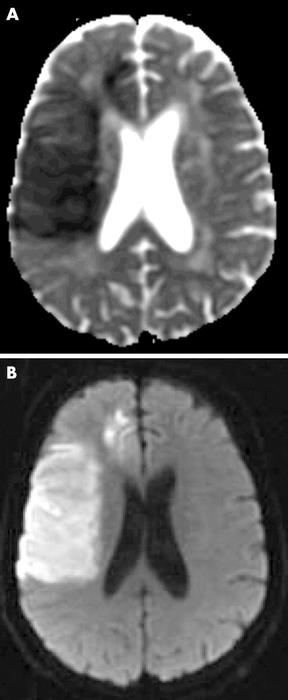

[Figure caption and citation for the preceding image starts]: Apparent diffusion coefficient (ADC) map and diffusion weighted MRI (DWI) of subacute stroke (day 3). Restricted diffusion of water leads to decreased signal on ADC, increased signal on DWIMuir KW et al. Neuro 2005; 76: iii19-iii28; used with permission [Citation ends].